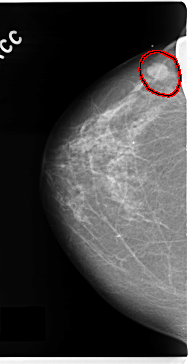

C_0128_1.RIGHT_CC

FILE: C_0128_1.RIGHT_CC.OVERLAY

TOTAL_ABNORMALITIES 1

ABNORMALITY 1

LESION_TYPE MASS SHAPE OVAL MARGINS MICROLOBULATED

ASSESSMENT 5

SUBTLETY 5

PATHOLOGY MALIGNANT

TOTAL_OUTLINES 1

BOUNDARY